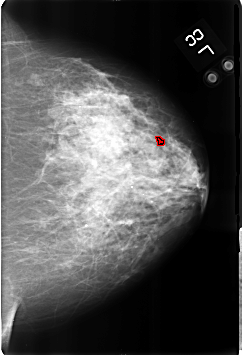

B_3174_1.LEFT_MLO

LEFT_CC LINES 4608 PIXELS_PER_LINE 3136 BITS_PER_PIXEL 12 RESOLUTION 50 OVERLAY

FILE: B_3174_1.LEFT_CC.OVERLAY

TOTAL_ABNORMALITIES 1

ABNORMALITY 1

LESION_TYPE CALCIFICATION TYPE ROUND_AND_REGULAR-LUCENT_CENTER-DYSTROPHIC DISTRIBUTION DIFFUSELY_SCATTERED

ASSESSMENT 2

SUBTLETY 4

PATHOLOGY BENIGN_WITHOUT_CALLBACK

TOTAL_OUTLINES 1

BOUNDARY